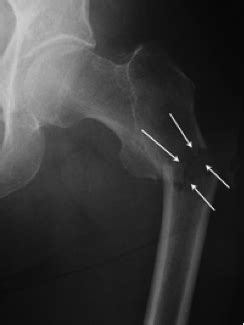

Quizlet is the easiest way to study, practise and master what you're learning.

All adolescents with an acute avulsion fracture of the lesser trochanter were included. Posterior hip dislocations account for 90% of hip dislocations a lesser trochanter fracture presents with groin pain, which radiates to the knee or posterior thigh, and worsens with hip flexion and rotation. Classification fractures in these regions can be classified as: The position of the lesser trochanter close to the head of the femur is one of the defining characteristics of the prozostrodontia. The patient had precursor symptom before onset during a ball juggling. There are two trochanters in the body: Will demonstrate fracture between the greater and lesser trochanter, with/out extension into the subtrochanteric region. Patients with fracture of femur between inferior margin of lesser trochanter and upper border of a square containing the distal end of the femur, closed and grade i. A trochanteric fracture is a bone break affecting the upper region of the femur or thigh bone, where two bony prominences known as the greater trochanter and lesser trochanter are found. Avulsion fractures of the lesser trochanter, greater trochanter, and iliac crest are less common.3. A fractured neck of femur (nof) is a common orthopaedic presentation. In the intramedullary nail shown here a spiral blade device is used to. Age, gender, mechanism of injury, fracture side, amount of displacement, and therapy were analyzed.

The iliopsoas musculotendinous unit can be injured from repetitive patients with lesser trochanter marrow edema (grade 2 or greater bsi) should refrain from running or impact activities until symptoms subside. Presenting symptoms of lesser trochanter avulsion fractures can be vague, but are usually localized to the groin and medial hip region. The greater trochanter and the lesser trochanter. Femoral head fractures are rare traumatic injuries that are usually associated with hip dislocations. The position of the lesser trochanter close to the head of the femur is one of the defining characteristics of the prozostrodontia. In the intramedullary nail shown here a spiral blade device is used to. Lesser trochanter bsis are less common compared with femoral neck bsis. Subtrochanteric fractures are fractures of proximal femur below lesser trochanter. Professional network for orthopaedic surgeons designed to improve orthopaedic education and. Yes a hairline fracture can heal by itself but the treatment modality depends on the age of the patient, type of fracture and the effected bone. Intertrochanteric fracture orif with cephalomedullary nail. Based on displacement distance of the lesser trochanter and whether the lesser trochanter was reduced operatively, patients were. A fractured neck of femur (nof) is a common orthopaedic presentation.